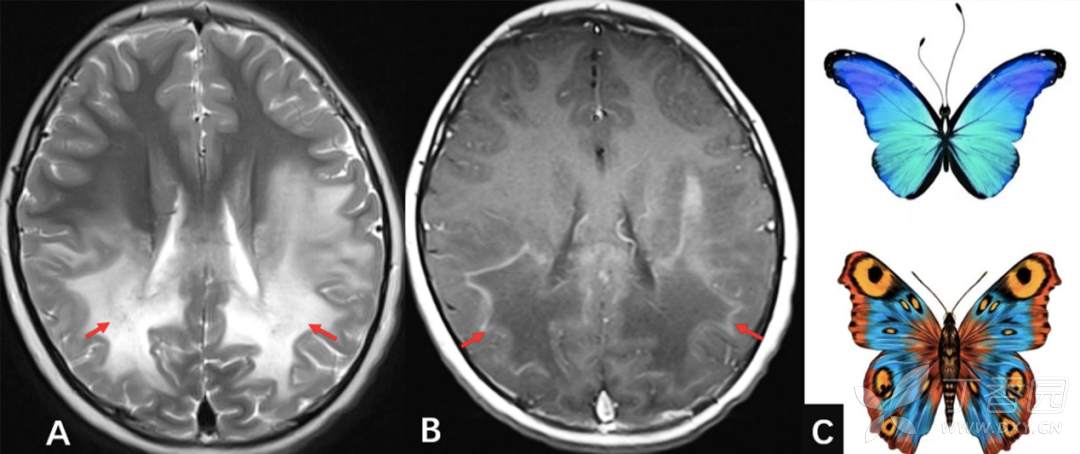

图 5-1. 肾上腺脑白质营养不良(ALD)

A. 轴位 T2WI 示双侧顶枕叶侧脑室周围对称性异常高信号,胼胝体亦受累,呈「蝴蝶翼」样改变(红色箭);B. 轴位 T1WI 增强扫描,病变周边可见强化呈「火焰状」改变(红色箭),提示病变处于活动期

图 5-2. 淋巴瘤

A. 轴位 T2WI 示胼胝体呈稍高信号,呈「蝴蝶翼」样改变(红色箭);B. 冠状位 T1WI 增强扫描,病变呈明显均匀强化呈「蝴蝶翼」样改变(红色箭头)

图 5-3. 胼胝体胶质母细胞瘤

A. 轴位 T1WI 增强扫描示胼胝体膝部可见花环状强化,呈「蝴蝶翼」 样改变(红色箭);B. 冠状位 T1WI 增强扫描,病变呈明显不均匀强化,内部可见无强化区(坏死)(红色箭头);C. 大体标本示意图,胶质母细胞瘤通过跨越胼胝体侵犯双侧大脑半球